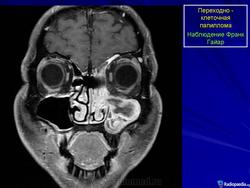

Переходно-клеточная папиллома.